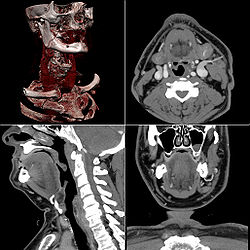

Neck

[edit]Contrast CT is generally the initial study of choice for neck masses in adults.[39] CT of the thyroid plays an important role in the evaluation of thyroid cancer.[40] CT scans often incidentally find thyroid abnormalities, and so is often the preferred investigation modality for thyroid abnormalities.[40]